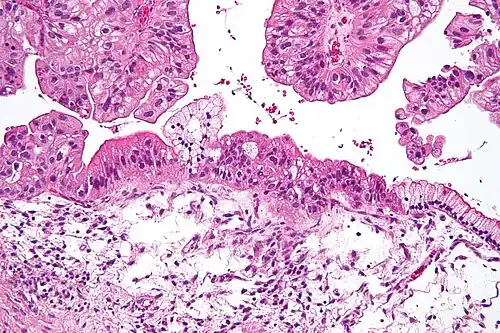

Micrograph of a mucinous ovarian tumor. H&E stain.

Benign mucinous tumors are typically multilocular (have several lobes), and the cysts have a smooth lining of epithelium that resembles endocervical epithelial cells with small numbers of gastrointestinal-type epithelial cells. Borderline and malignant mucinous tumors often have papillae and solid areas. There may also be hemorrhage and necrosis.

Cystadenocarcinomas (malignant tumors) contain a more solid growth pattern with the hallmarks of malignancy: cellular atypia and stratification, loss of the normal architecture of the tissue, and necrosis. The appearance can look similar to colonic cancer.